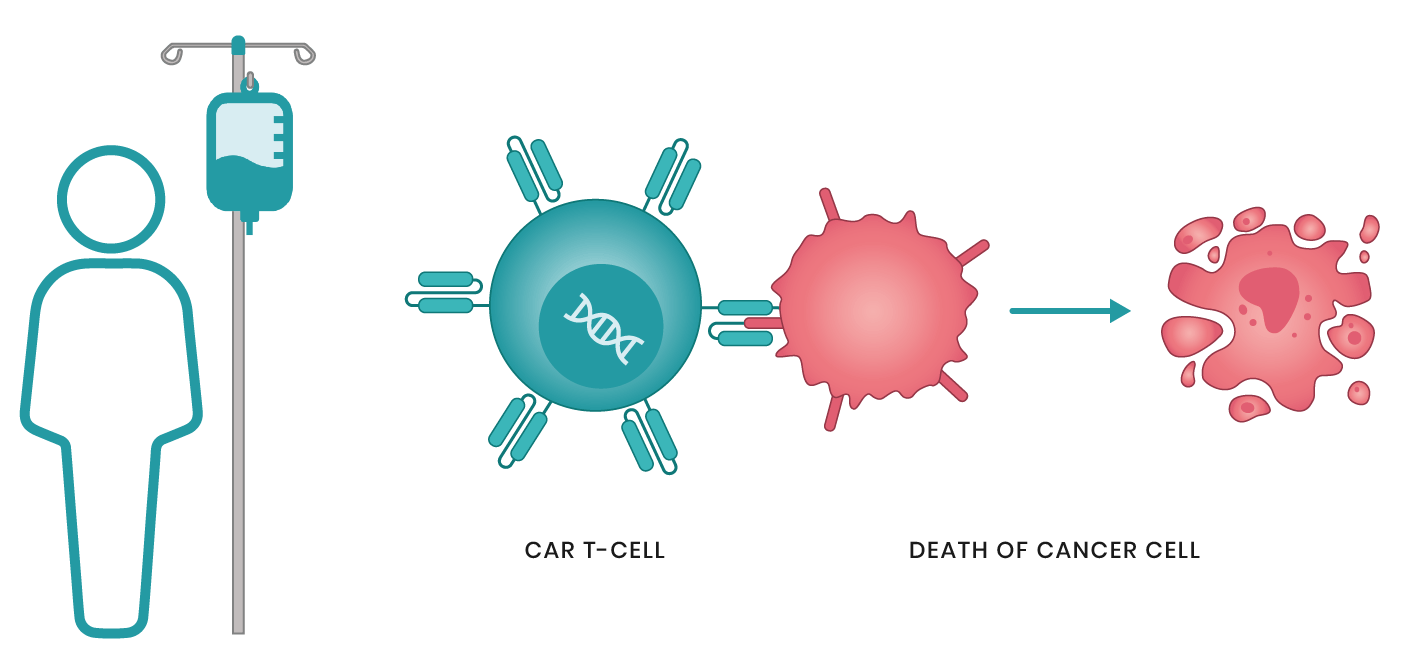

العلاج الخلوي التكيفي تم في عام 2017 الانتهاء من عدد من التجارب السريرية الكبيرة لتقنية علاج السرطان الجديدة، وهي العلاج بـ CAR T-Cell. وفقاً لنتائجهم، تمت الموافقة على اثنين من الأدوية: Kymriah و Yescarta. في الواقع يعد العلاج CAR T-Cell هو في وقت واحد علاجاً جينياً، ومناعياً، وخلوياً. تغير هذه التقنية خلايا الدم البيضاء للمريض بطريقة تمكنها من التعرف على الخلايا السرطانية وتدميرها. على الرغم من عدد من الآثار الجانبية، سيكون العلاج CAR T-Cell فعالاً بالنسبة لمعظم المرضى الذين لا يتقبلون أي علاج آخر أو في حالات الانتكاس.

يستخدم العلاج الخلوي CAR-T الكريات البيض الخاصة بالمريض لمكافحة الخلايا السرطانية. وفقاً لذلك، فإن المرحلة الأولى من العلاج تتمثل في الحصول على الكريات البيض للمريض – وهذا يحدث أثناء أخذ عينات الدم خارج الجسم وفصادة الكريات البيض (الحصول المباشر على الكريات البيض من الدم). بالإضافة إلى جمع الكريات البيض، فإن تكوينها النوعي مهم. وعلى وجه الخصوص، تتم إزالة الوحيدات من العدد الكلي للكريات البيض، والتي تعوق في البيئة الطبيعية تنشيط وتكاثر الخلايا التائية اللازمة للعلاج العلاج الخلوي CAR-T.

بعد تلقي كريات البيض المحدثة التي تحتوي على CAR، يتم تكاثر الخلايا في المختبر. يعد إدخال عدد كاف من الكريات البيض النشطة مع CAR شرطاً أساسياً للعلاج الفعال. هذه المرحلة المختبرية هي الأكثر استهلاكاً للوقت ويمكن أن تستغرق ما يصل إلى 22 يوماً.

قبل إعادة إدخال الكريات البيض المحتوية على CAR يتم إعطاء المريض دورة من العلاج الكيميائي تهدف إلى تقليل عدد الكريات البيض الخاصة بهم. تسمح هذه الظروف بتضاعف الكريات البيض “الخاصة” التي يتم إدخالها بشكل مكثف أكثر. عند تنفيذ العلاج الخلوي CAR-T، فإن دورة واحدة فقط من معالجة جينوم الكريات البيض تكون كافية. في المستقبل تتكاثر خلايا الدم البيضاء بنفسها في دم المريض، مما يوفر مناعة دائمة ضد الانتكاس.